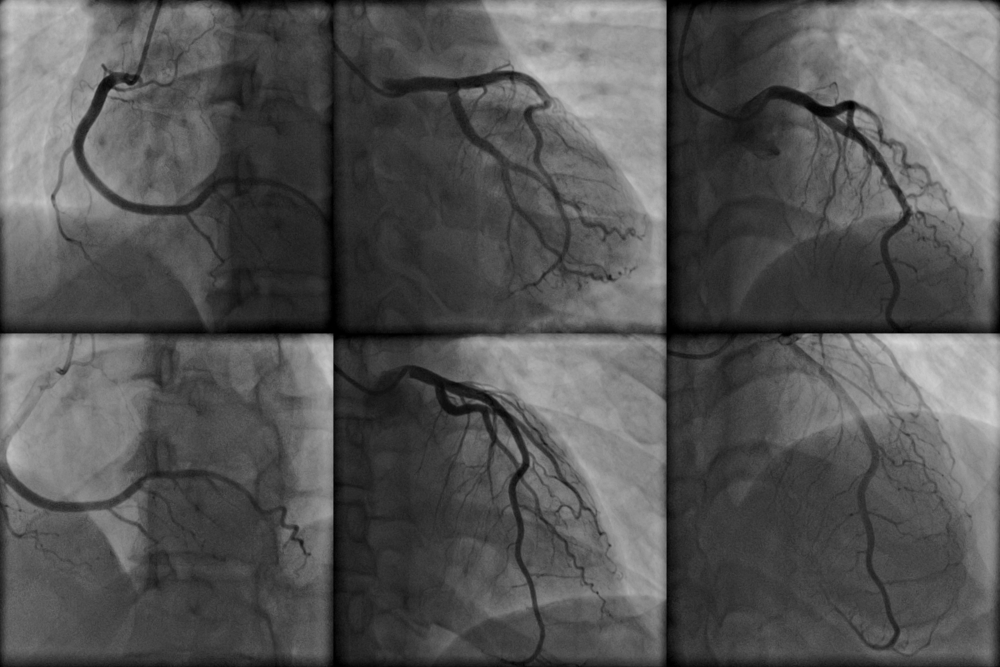

- Для выполнения ангиографии в катетер вводится рентгеноконтрастное средство, делающее видимыми желудочки и коронарные сосуды. Специалист изучает их состояние, выполняет снимки и делает необходимые заключения. При выполнении снимков врач может попросить пациента задержать дыхание, глубоко вдохнуть или покашлять.

- ангиография – для визуализации камер сердца, коронарных сосудов, легочных артерий и аорты;